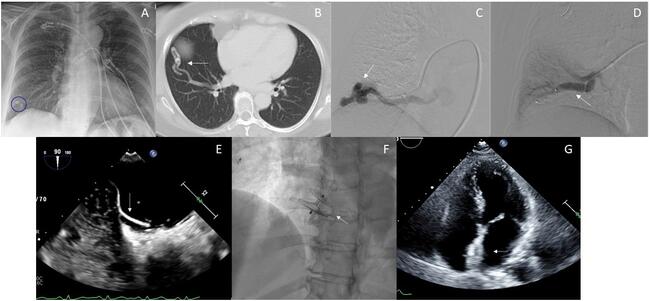

A 64-year-old woman presented with acute onset left-sided facial droop, left upper extremity paresis, and aphasia. Magnetic resonance imaging demonstrated acute infarction of the right thalamus. A chest x-ray revealed a 1.7-cm nodular opacity at the right lung base (Figure A). A contrast-enhanced computed tomography (CT) revealed a right lower lobe (RLL) pulmonary arteriovenous malformation (AVM) (Figure B), and a transthoracic echocardiogram (TTE) with agitated saline showed bubbles in the left atrium.

The patient underwent pulmonary angiography, which demonstrated a simple AVM arising from a branch of the RLL pulmonary artery (Figure C), with subsequent embolization. Via a 10F femoral venous sheath, the pulmonary arterial system was catheterized using a 7F guide catheter and 4F Glidecath (Terumo). A 12-mm Amplatzer AVP II plug (Abbott) was inserted for embolization (Figure D). Repeat TTE continued to show bubbles in the left atrium. A transesophageal echocardiogram revealed a patent foramen ovale (PFO) with atrial septal aneurysm (Figure E). The patient was referred for concomitant PFO closure. A 6F multipurpose guide catheter was advanced across the PFO into the pulmonary vein. An 8F Amplatzer intravascular delivery system was subsequently advanced across the inter-atrial septum over a stiff wire, and a 30-mm Amplatzer PFO Occluder (Abbott) was deployed and released (Figure F) utilizing intracardiac echocardiography guidance. Repeat TTE (Figure G) and CT demonstrated the absence of bubbles in the left atrium and complete occlusion of the pulmonary AVM, respectively.